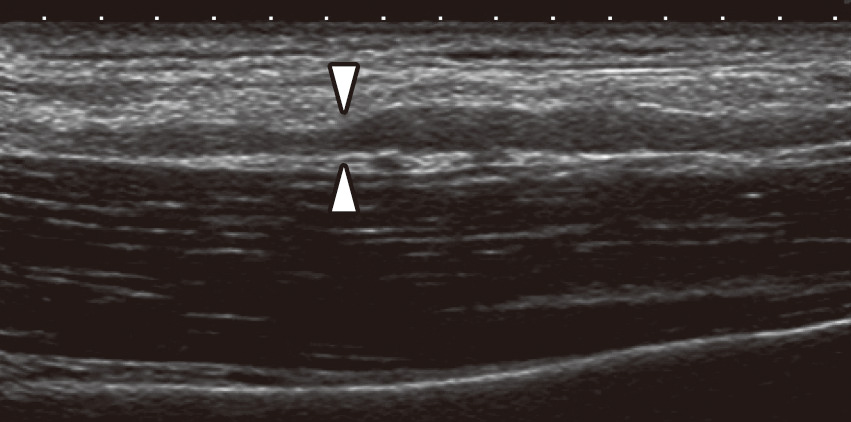

少し豊富な贈り物 91RxeAK12UL.jpg 健康+医学

少し豊富な贈り物 91RxeAK12UL.jpg 健康+医学

91RxeAK12UL.jpg,

91RxeAK12UL.jpg, 朝倉内科学第12版』待望の全面改訂。鍼灸医学大辞典 デスク版/医歯薬出版/森和(大型本)。PC・タブレットでも閲覧可能!,